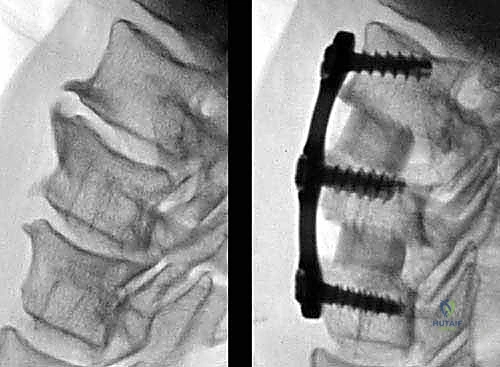

الخطوة 7: التثبيت المعدني (Instrumentation)

لضمان الاستقرار الفوري ومنع حركة الطعم العظمي حتى يكتمل الالتحام (والذي يستغرق أشهراً)، يقوم الدكتور هطيف بتثبيت شريحة معدنية صغيرة من التيتانيوم على الجزء الأمامي من الفقرتين باستخدام براغي دقيقة.

الخطوة 8: الإغلاق التجميلي